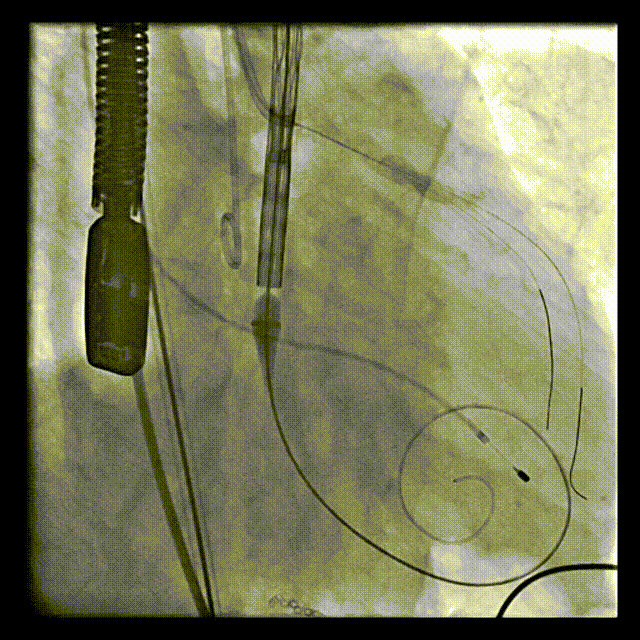

在医务处协调下,心胸外科、麻醉科、重症医学科、体外循环组做详尽预案的充分准备下,张俊杰教授成功完成了这一例高难度的TAVR+PCI手术,在全麻和ECMO湿备的保护下,术中首先采用双支架技术成功处理LAD/D1复杂分叉病变,随后成功植入VitaFlow 30瓣膜,术后植入IABP辅助患者的心功能的恢复,并转ICU进一步治疗。

主动脉根部造影示重度主动脉瓣反流

瓣膜释放前定位

瓣膜稳定释放

释放后造影:瓣膜位置良好,无瓣周漏